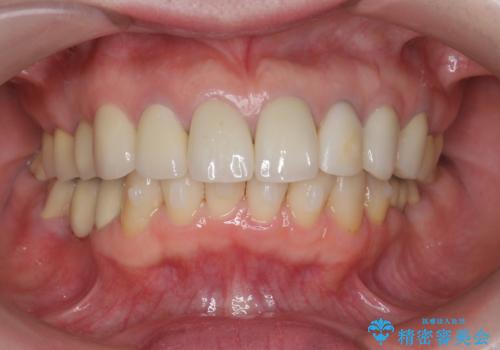

下顎前歯の突き上げについて

噛み合わせが強くまた下顎に前歯にもガタつきが認められる場合、歯ぎしりやくいしばることで上顎前歯に大きな力がかかり歯の破折やクラウン損傷の大きなリスクとなることがあります。

このおようなリスクを最大限回避するためにも、咬合調整や小矯正により大きな力が上顎前歯にかからないような環境を整えることが大切です。